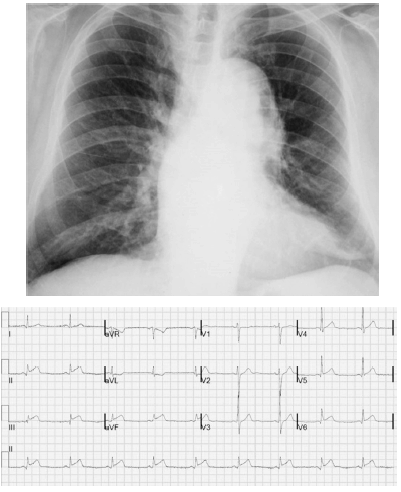

Um paciente de 68 anos de idade e hipertenso apresentava dor torácica lancinante na parede anterior com irradiação para a região cervical, de forte intensidade e sem alívio com analgésicos comuns havia duas horas. No exame físico, ele se encontrava sudorético e acianótico, com saturação de oxigênio em ar ambiente de 90%, pressão arterial de 182 mmHg × 112 mmHg e frequência cardíaca de 88 bpm. Apresentava ritmo cardíaco regular em dois tempos, com sopro diastólico (+/4) no segundo espaço intercostal à direita. Os valores da troponina ultrassensível foram normais. A radiografia de tórax e o eletrocardiograma desse paciente estão mostrados a seguir.

Com relação ao caso clínico hipotético anterior, julgue o item que se segue.

Recomenda-se o uso de nitroprussiato de sódio para a redução de até 25% da pressão arterial média em uma hora.

A angiografia coronariana é o método de escolha para a confirmação diagnóstica.

A dupla antiagregação plaquetária e a heparina não fracionada devem ser iniciadas na admissão.